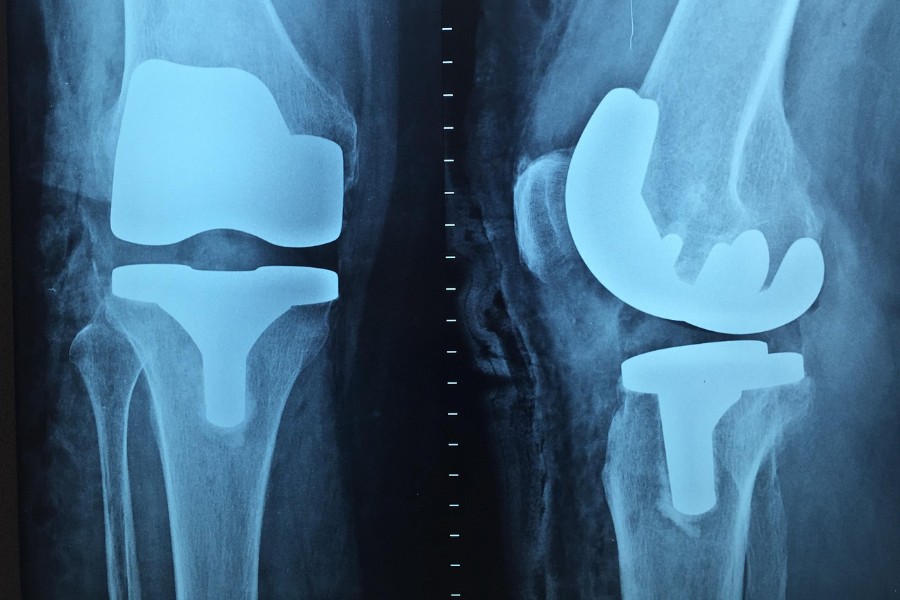

Когда операция по замене сустава неизбежна?

Решение об эндопротезировании (как говорят пациенты, «замене сустава»), зависит от целого ряда факторов: степени разрушения хряща, болевого синдрома, ограничения подвижности и общего состояния.

Если консервативное лечение не дает результата, боль мешает жить и работать, а разрушение сустава достигло критической точки, то чаша весов склоняется в сторону хирургического вмешательства. Обычно это последние стадии остеоартрита, когда другие методы уже неэффективны.

Большинство пациентов после замены сустава возвращаются к активной жизни, работают и путешествуют.

Конечно, есть ограничения. Например, противопоказаны чрезмерные физические нагрузки. Но в целом эндопротезирование и рекомендации врача по части реабилитации позволяют достичь высокого уровня функциональности.